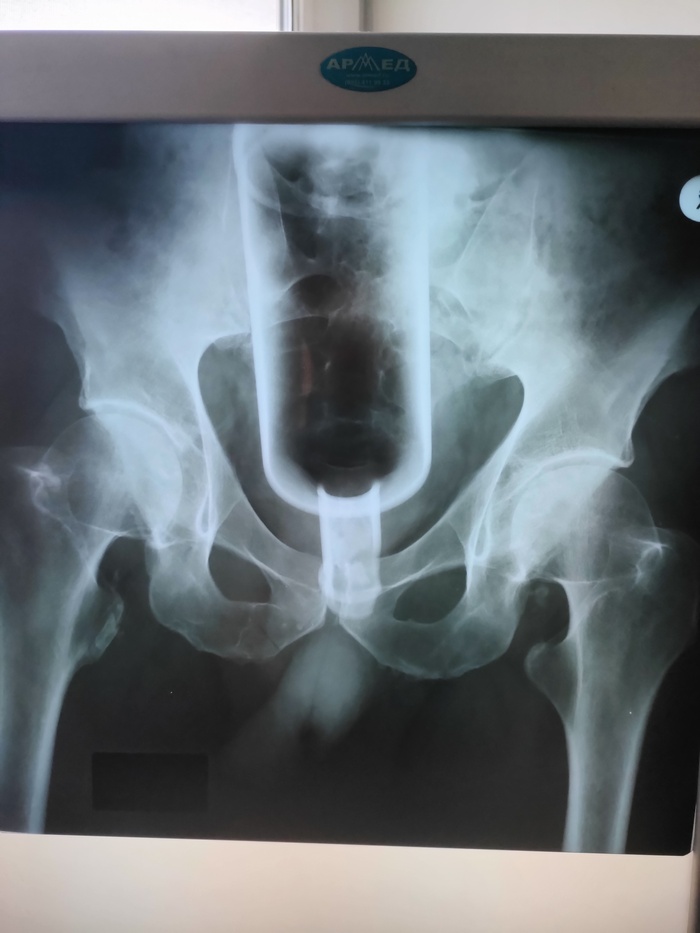

Назначил снимки и пошел ожидать не до конца осознавая приближающееся веселье. Минуты ожидания превращались в часы, чай перестал быть вкусным, все проблемы ушли на второй план, ведь у нас тут у человека в жопе бутылка! Ворвавшись без стука санитар из приемника сует мне снимок с улыбкой и говорит, ну, ну смотрите же доктор какая там красота, а там и правда красота, кстати вот вам она

НИ ХУААА сказал я с китайским акцентом на всю ординаторскую! Санитар рассмеялся и сказал что тоже ах...ел когда увидел. Первая моя мысль - бля, а тут 0.5 или 0.7?!🤔 Вторая мысль, это то что бутылка дном кверху, каааак так её засунуть?!! Третья мысль что горлышко то к нам передом, а значит можно будет зацепиться чтобы вытащить.